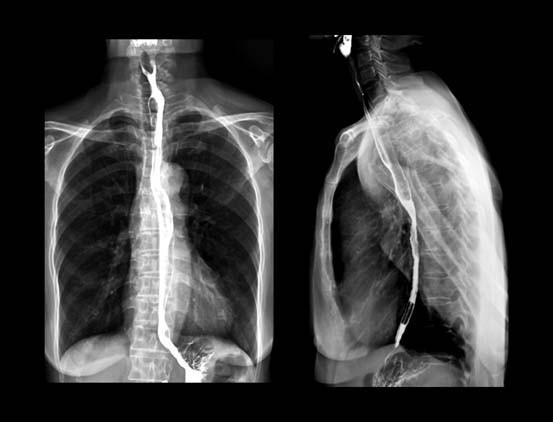

Bu başarı, Andrew’un artık ameliyat edilebileceği anlamına geliyordu; ‘özofajektomi’ yapılacaktı yani sağ akciğeri söndürülecek ve yemek borusunun yaklaşık 15 santimetrelik kısmı kesilip atılacaktı.

Sekiz saat süren ve oldukça invaziv olan bu ameliyat, vücudunda göğüs kafesinden göbeğinin altına ve sırtına kadar uzanan devasa bir iz bıraktı. İyileşme süreci çok zordu ama yapılan son tomografi taraması, kanserden eser kalmadığını gösterdi.